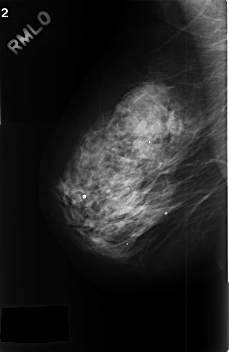

C_0379_1.RIGHT_MLO

RIGHT_CC LINES 4568 PIXELS_PER_LINE 2936 BITS_PER_PIXEL 12 RESOLUTION 50 NON_OVERLAY

RIGHT_MLO LINES 4568 PIXELS_PER_LINE 2968 BITS_PER_PIXEL 12 RESOLUTION 50 NON_OVERLAY